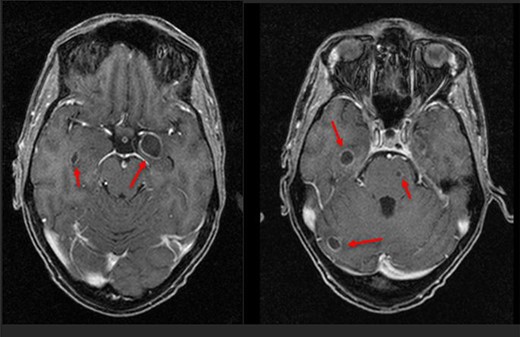

Six days following his initial follow-up, this patient was brought to the emergency department by ambulance following a witnessed seizure. He was distressed and confused on arrival but otherwise apyrexial with a non-tender abdomen. Initial blood tests were as follows: haemoglobin 82 g/l, WCC 25.3 × 109/l, CRP 284 mg/l, Plts 477 × 109/l, Neuts 23.8 × 109/l, Lymph 0.6 × 109/l, bilirubin 30 μmol/l, albumin 266 g/l, ALT 133 IU/l and alkaline phosphatase 914 IU. All other blood tests were non-contributory. Blood cultures isolated a Streptococcus intermedius bacteraemia. CT revealed four large hepatic abscesses with the largest in segment 4b measuring 92 × 90 mm and a right hepatic vein thrombus. Three of the liver abscesses were drained to completeness by interventional radiology (IR). Magnetic resonance imaging (MRI) showed several focal restricting intraparenchymal brain lesions, posterior left temporal lobe measuring 1.7 cm and multiple smaller lesions within the right frontal, right para-ganglionic region, right parahippocampal, left uncal regions, right cerebellar hemisphere and left pons (Figs 1 and 2) consistent with brain abscesses.

An MRI head then showed that the intra-cerebral cavitating lesions were solidifying and reducing in size. There were also several new microabscesses present in the left temporoparietal region. A further 5-week intraveneous (IV) antibiotic therapy solidified the new lesions.